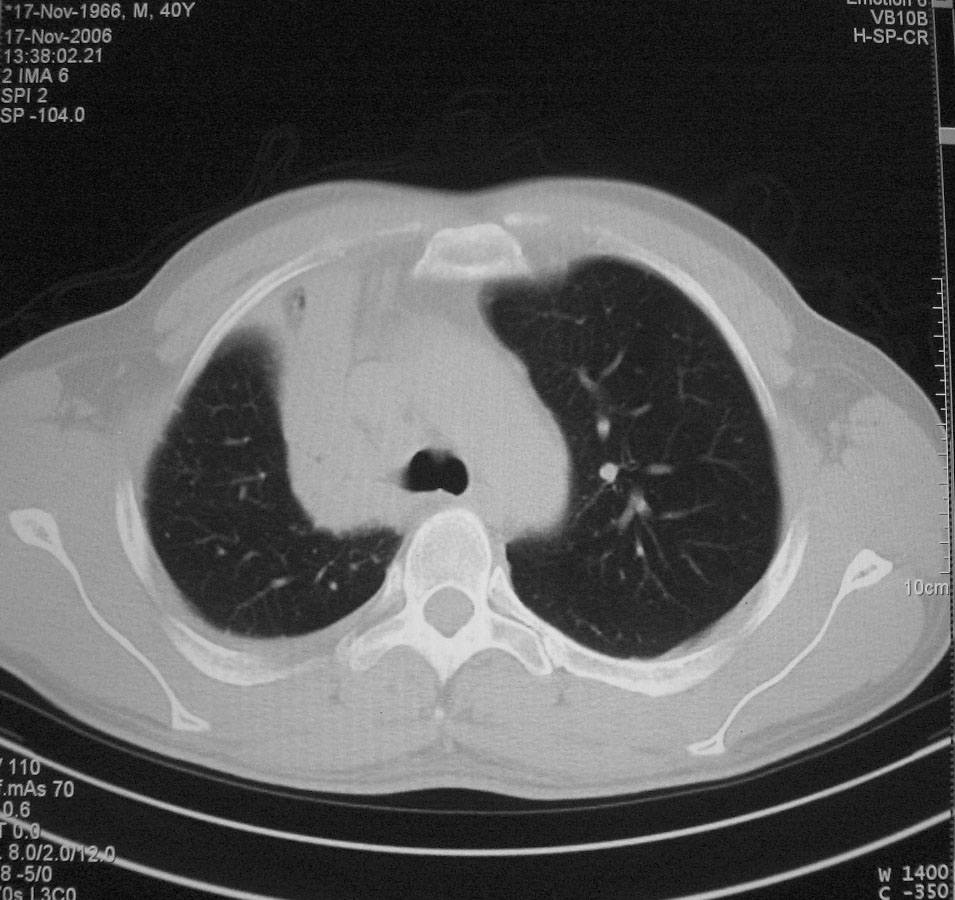

标题: CT5485:[原创]肺部占位请讨论

右肺上叶中央型肺癌并上叶肺不张、纵隔淋巴结肿大

右上叶支气管肺癌并右上叶阻塞性不张,右侧少量胸腔积液.

右肺上叶中央型肺癌并上叶肺不张、纵隔淋巴结肿大.右侧少量胸腔积液。

右上肺中心型肺癌并肺不张,纵膈淋巴结肿大。右侧少量胸腔积液。

右肺上叶不张,考虑中央型肺癌。右侧胸膜肥厚

右肺上叶中央型肺癌并阻塞性炎症、阻塞性肺不张……